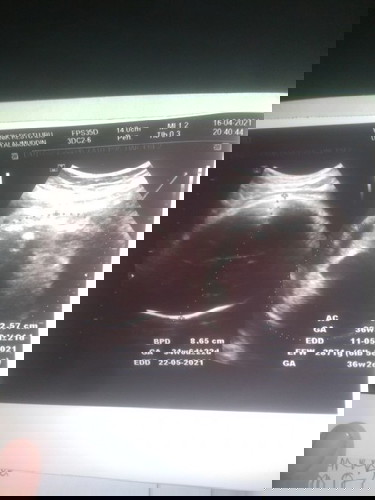

Bun kemarin aku habis usg kok beda ya perhitungan usg sma apk Apk 37 usg 36 dan hpl pun jadi mundur

krn kalo apk itu diperhitungkan dr hpht bun byasa disebut usia kehamilan. kalo hasil usg bunda diatas dihitung dr lingkar perut dan lingkar kepala yg biasa disebut usia janin atau usia kandungan. memang biasa selisih maksimal 2mgg.

Baca lagiYg jd patokan usg pas trimester awal bun. Usg di trimester akhir ngukur ny dr besar kecil ny kepala sama perut janin. Makin besar bbj ny makin maju/ mundur hpl ny. Saya jg kmrin gt. Bbj pas usg lebih kecil dr apk. Jd hpl saya mundur. Tp alhamdulillah lahir ny pas sesuai hpl usg pertama.

gapapa bund, kalo di aplikasi kan bunda ngitungnya pake HPHT. kalo usg kan kadang ngikutin ukuran bayinya, jadi ngikutin yg terdekteksi sama alat usg. malahan aku jd maju pas di usg, karena ukuran bayinya melebihi usia hpht,jd di itungnya sesuai sama ukuran bayi biasanya.